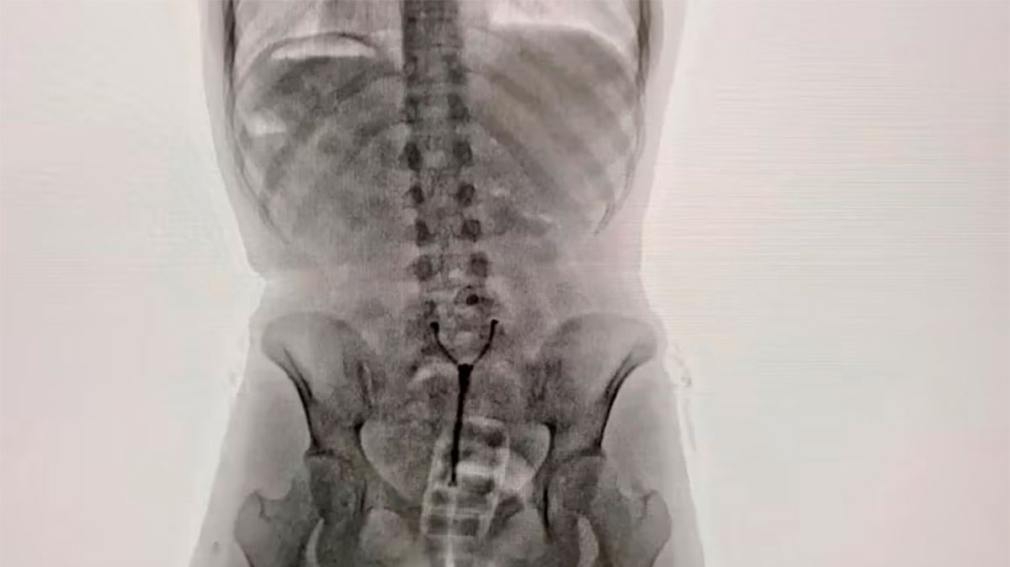

Imágenes son impactantes. La joven de 20 años que fue descubierta tras un control con equipo de rayos X en Ezeiza.

Ante las consultas, la pasajera “respondió de manera incongruente y dubitativa”, lo cual levantó aún más las sospechas. Ante esta situación, agentes de la Policía de Seguridad Aeroportuaria (PSA), conjuntamente con funcionarios de la Dirección General de Aduanas y personal de AIRCOP, procedieron a realizarle un control corporal no invasivo mediante equipo de rayos X (Body Scan) y delante de la presencia de testigos.

La inspección dio pie a la revelación del delito: en las imágenes los efectivos observaron la posible presencia de elementos extraños en el organismo, concentrados en su zona genital.

En consecuencia, con la orden judicial en mano, la pasajera empezó a ser requisada hasta que en un momento confesó espontáneamente y manifestó que transportaba un paquete introducido vía vaginal. Concretamente, había introducido en su cuerpo un profiláctico con 11 cápsulas de cocaína, de aproximadamente 10 gramos cada una.

Como parte del procedimiento, la joven fue trasladada al Hospital de Ezeiza. Allí, bajo custodia de la PSA, estuvo incomunicada mientras evacuaba las cápsulas detectadas en las imágenes del escáner, las cuales finalmente fueron muchas más que 11: tenía otras 67 cápsulas en el sistema digestivo. En total, en su cuerpo llevaba 742 gramos de esa droga.